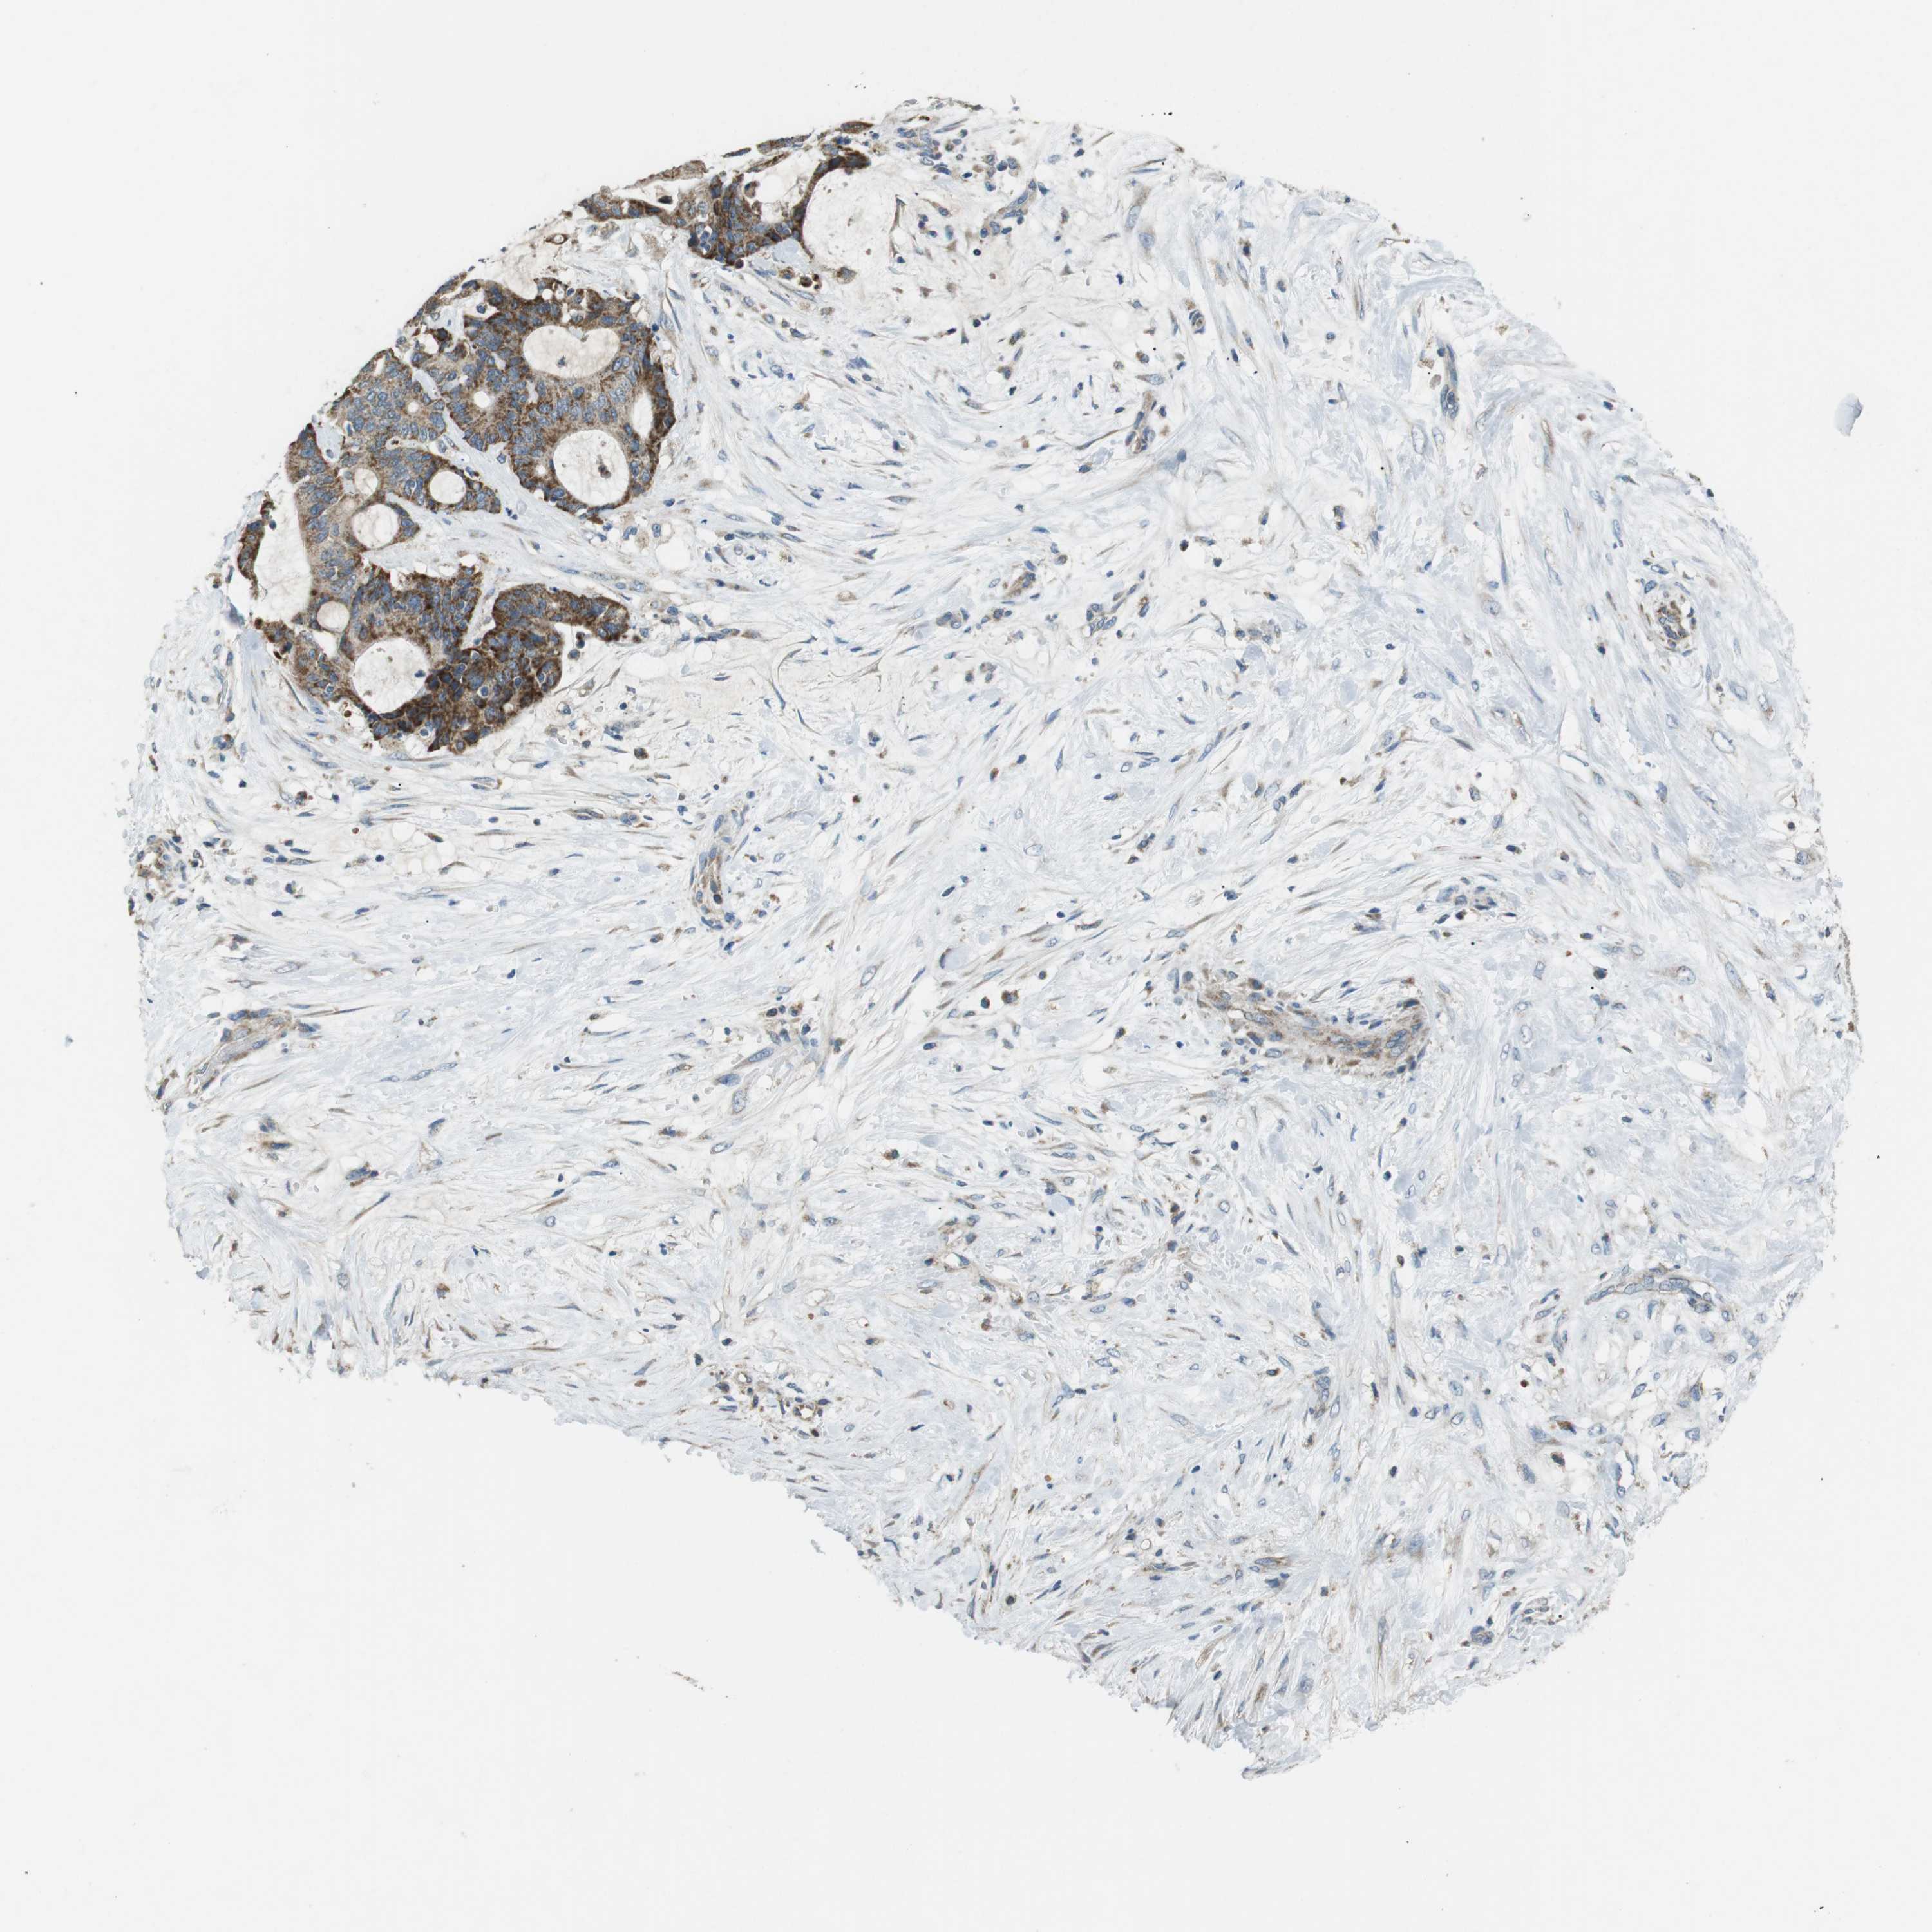

LIVER CANCER - Protein expressioni

A mouse-over function shows sample information and annotation data. Click on an image to view it in a full screen mode. Samples can be filtered based on level of antibody staining by selecting one or several of the following categories: high, medium, low and not detected. The assay and annotation is described here.

Note that samples used for immunohistochemistry by the Human Protein Atlas do not correspond to samples in the TCGA dataset.

Antibody stainingi

Antibody staining in the annotated cell types in the current human tissue is reported as not detected, low, medium, or high, based on conventional immunohistochemistry profiling in selected tissues. This score is based on the combination of the staining intensity and fraction of stained cells.

Each image is clickable and will lead to virtual microscopy that enables deeper exploration of all samples and also displays staining intensity scores, fraction scores and subcellular localization as well as patient and tissue information for each sample.

Antibody CAB016358

Staining

High

Medium

Low

Not detected

Intensity

Strong

Moderate

Weak

Negative

Quantity

>75%

75%-25%

<25%

None

Location

Nuclear

Cytoplasmic/membranous

Cytoplasmic/membranous,nuclear

Cholangiocarcinoma

Carcinoma, Hepatocellular, NOS